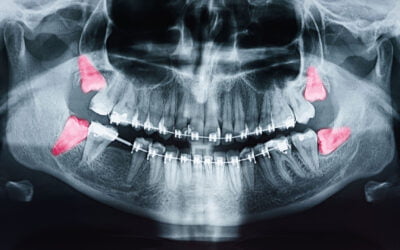

Seeking Wisdom About Teeth

In the 17th century, they were called “teeth of wisdom.” Since the 19th century, we’ve been calling them “wisdom teeth.” Whatever name you choose, we are talking about the set of third molars that appear in your mouth — two on the top and two on the bottom — typically...